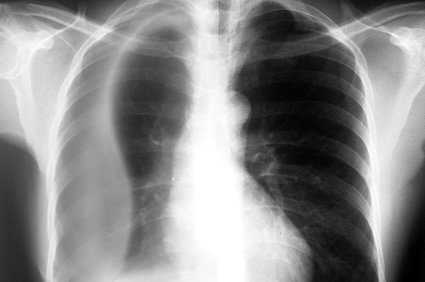

O derrame pleural, também chamado popularmente de “água na pleura” ou "água no pulmão" - termos que se popularizaram, mas que geram grande confusão, já que se referem no popular tanto à presença de água na pleura quanto à presença de água no pulmão - é caracterizado pelo acúmulo excessivo de líquido no espaço entre essas duas lâminas. Portanto, deve-se ter o cuidado de não o confundir com a chamada “água no pulmão” que se refere à condição caracterizada pelo acúmulo de líquido dentro do pulmão (edema pulmonar), e não no espaço entre as pleuras.

Se o derrame for de pequena monta, o paciente pode não ter sintomas. Se for moderado ou grande, ou se houver inflamação ativa, os sintomas podem incluir falta de ar, dor no peito ao respirar profundamente, febre e tosse seca. O excesso de fluido no espaço pleural pode prejudicar a inspiração, perturbando o vácuo funcional e aumentando hidrostaticamente a resistência contra a expansão pulmonar, resultando em um pulmão total ou parcialmente colapsado.

O médico deverá fazer um levantamento do histórico clínico do paciente e dos sintomas que ele relata, bem como fazer um exame físico que deverá incluir auscultar seu tórax com um estetoscópio. Para confirmar o diagnóstico, precisará fazer exames de imagem, como radiografias do tórax em várias posições, tomografia computadorizada e ultrassonografia.